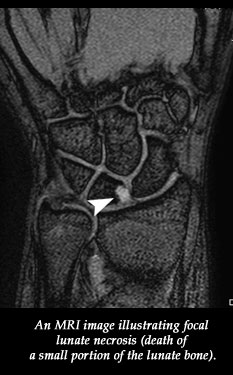

Dwek's study looked at 125 MRI exams taken of adolescents at Rady Children's Hospital in San Diego over a two-year period. MRI, or magnetic resonance imaging, is a common non-invasive technology used to diagnose injuries to bones, ligaments, and other tissues deep within the body. Their analysis revealed that a dozen of these adolescents were female gymnasts with chronic wrist or hand pain.

They then examined the MRI scans carefully for injuries to the bones and soft tissues, uncovering, a spectrum of associated injuries. Included among these was a classic chronic injury that occurs in children and adolescents known commonly as gymnasts' wrists.

These sorts of injuries are probably due to chronic repetitive trauma, says Dwek. They include abnormal bone growth or abnormal bone loss. There were girls in the study who had unusual inflammation in their hands. Their MRIs also showed a flattening of the knuckles and knuckle "necrosis," or tissue death.